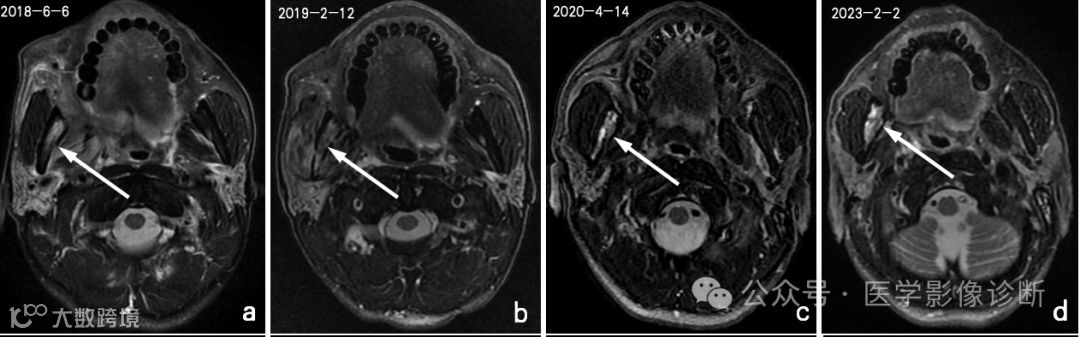

患者,男性,56岁,放疗后患有右口咽癌。

不同时期的四次核磁共振成像显示右下颌骨有异常信号。前两次报告(a、b)均未提及异常信号,说明存在感知错误(漏诊)。在第三次检查(c)中,放射科医生发现了异常信号,但误认为是骨转移,说明存在认知错误(误诊)。患者自2018年以来经常牙龈肿痛的临床查体和治疗情况被遗漏,经过抗炎治疗后,这种症状得到了很大改善。诊断应为右下颌骨骨坏死伴骨髓炎,但放射科医生因不熟悉放疗并发症而导致诊断偏差。